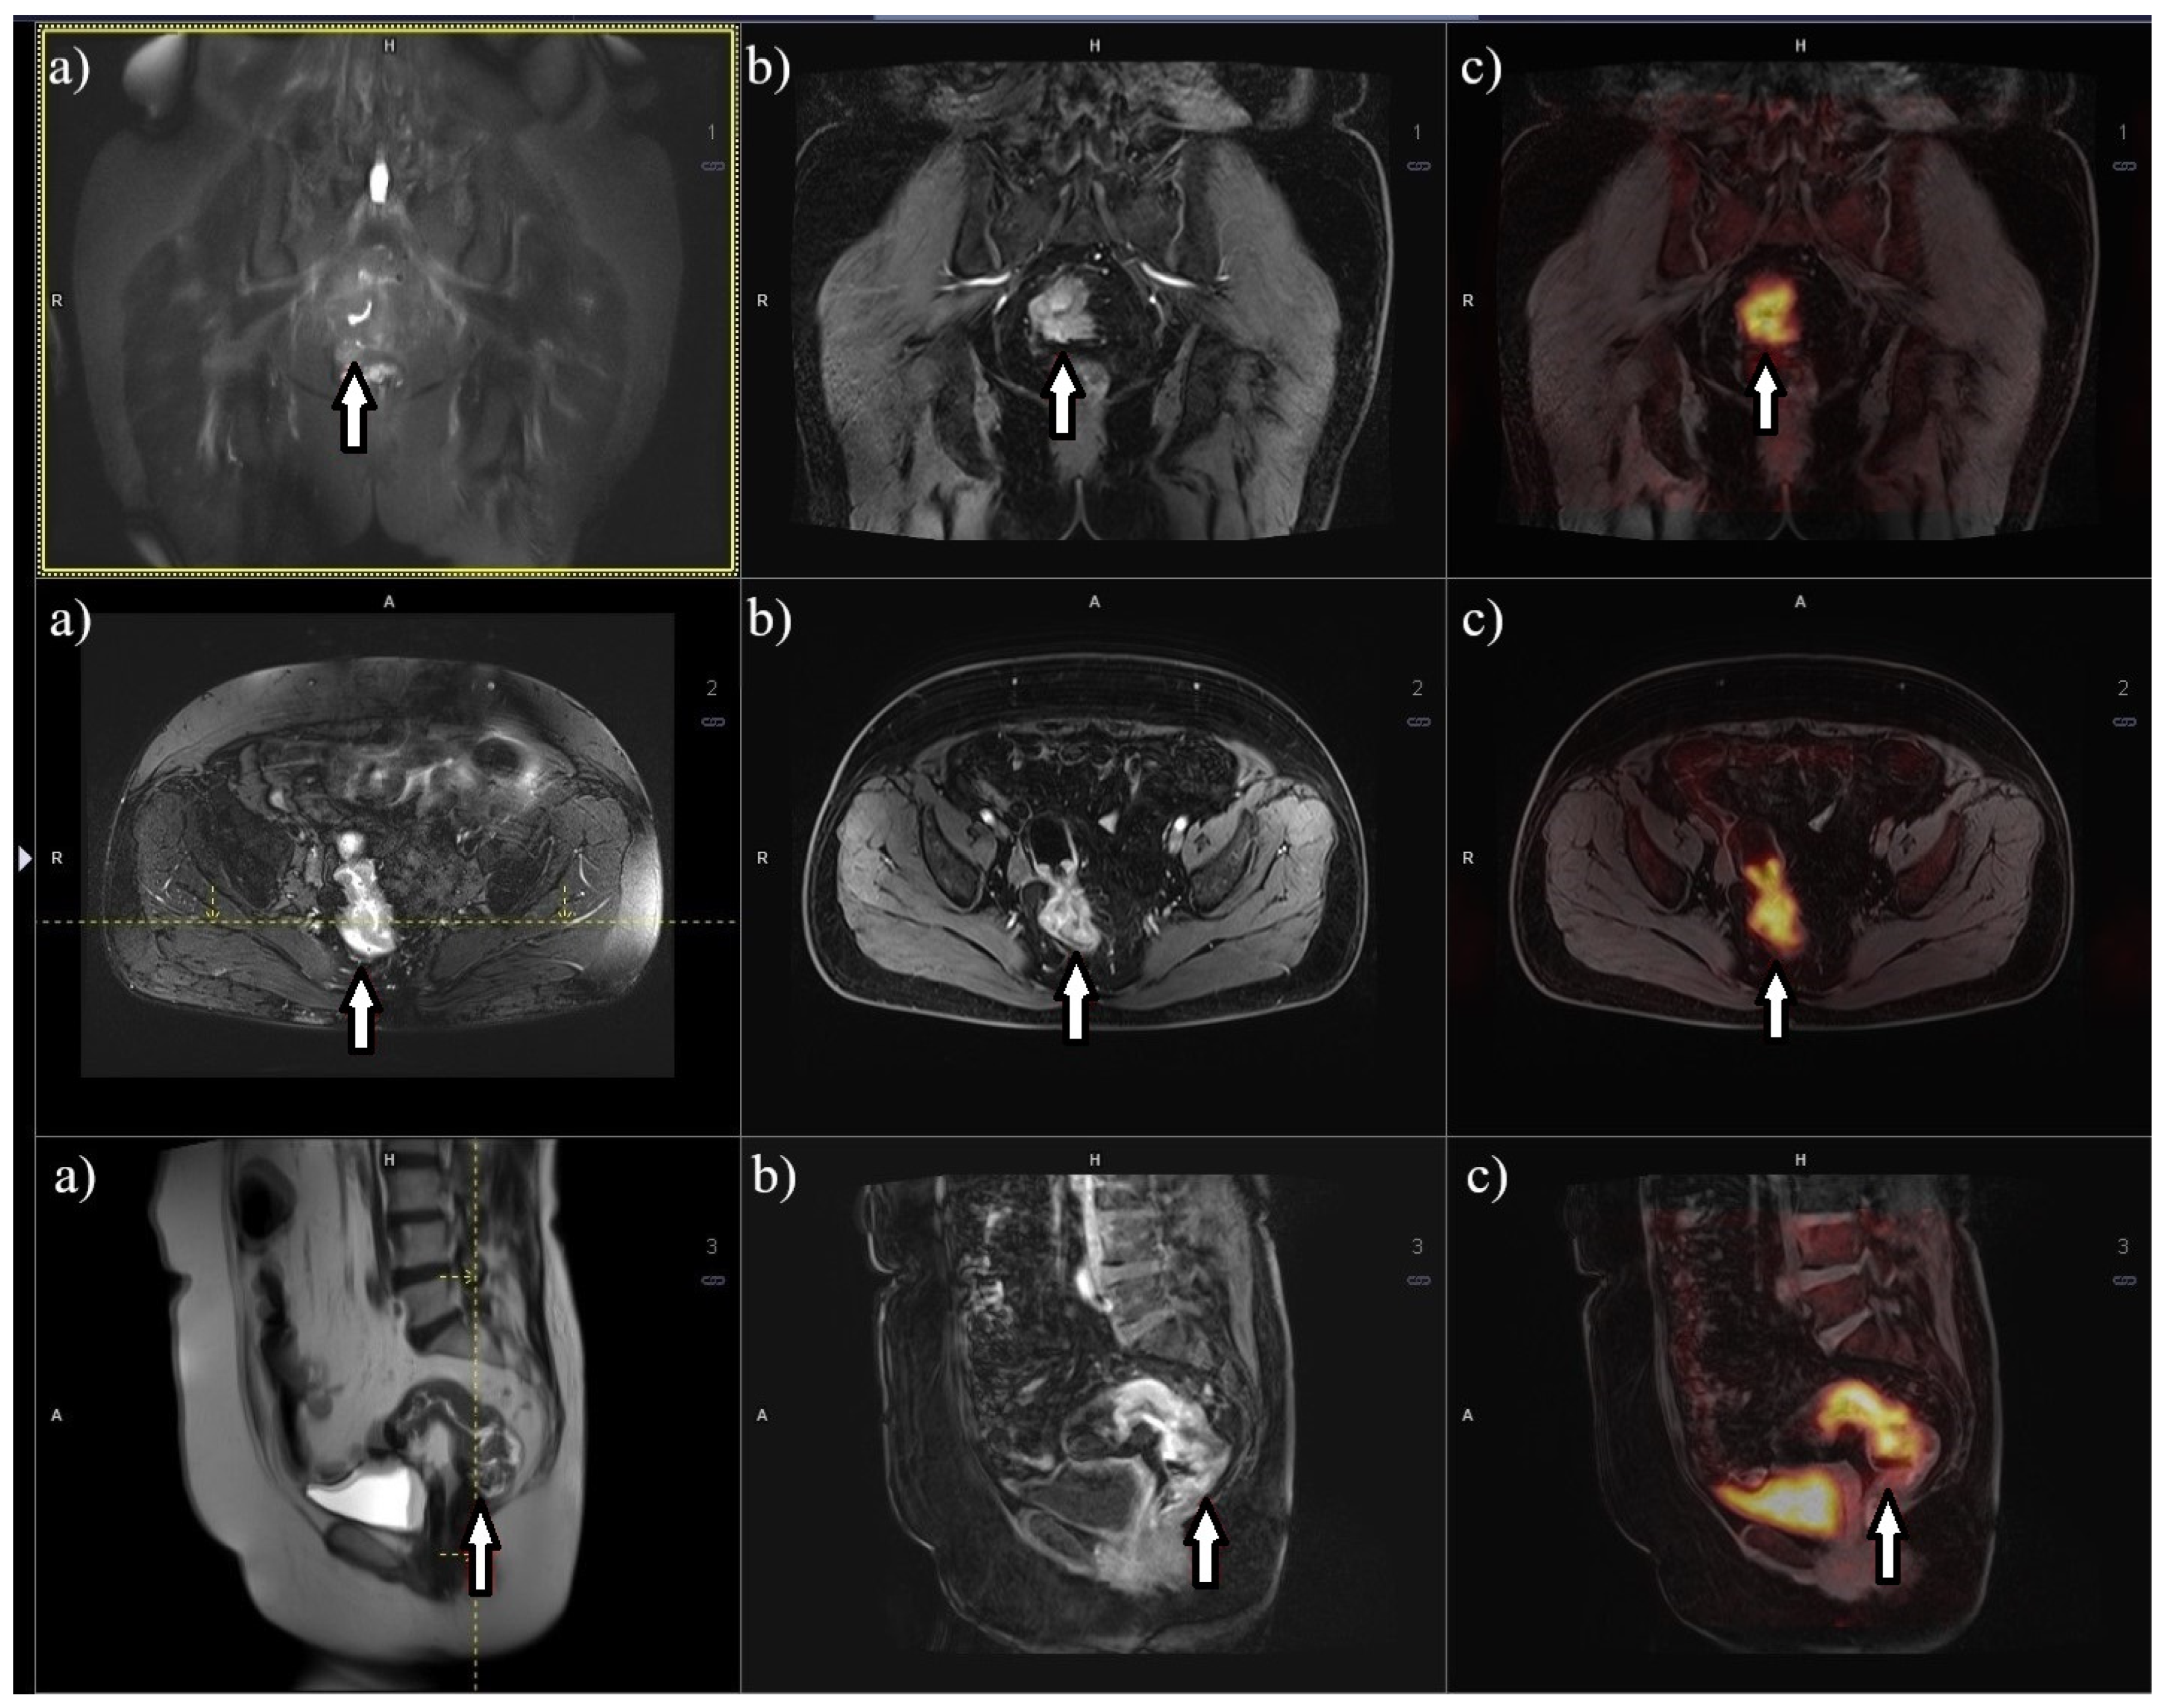

8. Metabolic Imaging 18F-FDG PET/MRI